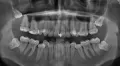

Помогите, пожалуйста, разобраться с необходимостью и срочностью удаления восьмерок. Мне 28 лет, восьмерки не прорезавшиеся, за исключением левой нижней (недавно прорезался один холмик). Не болят, не беспокоят. Доктор советует удалять все четыре. Я планирую беременность, и хотела бы заняться вопросом зубов мудрости через пару - тройку лет.

Возможно ли отложить удаление на этот срок? И не сместятся ли все остальные зубы после удаления восьмерок (не разъедутся)? Особенно за верхний зубной ряд переживаю, ношу ретейнер после выравнивания.

Вы считаете ровно наоборот. Естественно, все четыре зуба необходимо удалить. Наверху начнется скученность зубов, возможна травма и повреждение седьмых зубов, так как места для восемнадцатого и двадцать восьмого зубов нет. Конечно удаляйте и не думайте, тем более, что планируете беременность. Учтите, что во время беременности и лактации невозможны манипуляции с применением анестезии и возможно антибиотиков. А рост восьмых зубов, как правило сопровождаются болями и дискомфортом.